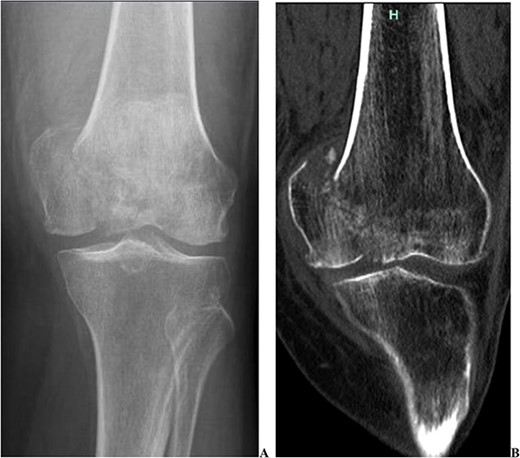

We present the case of a 76 year old Hispanic female previously managed for tri-compartmental osteoarthritis and lateral condyle insufficiency fracture of the left knee. She was being managed conservatively; however, the pain began to affect her well-being and activities of daily living (ADL). Most recently the patient suffered a mechanical ground level fall resulting in an ipsi-lateral medial condyle fracture as seen in Fig. 1. Single staged left knee medial condyle ORIF and CCK arthroplasty through a medial para-patellar approach was performed. The medial condyle fracture was reduced and stabilized using a 5-hole distal fibula locking plate in buttress mode. After fracture stabilization, a CCK arthroplasty was performed. Immediate post-operative imaging is seen in Fig. 2. Intra-operative photos are demonstrated in Fig. 3. The patient was made non-weight bearing for 2 weeks followed by weight bearing as tolerated (WBAT). An early weight bearing protocol was used given the majority of forces during ambulation would be placed through the total knee implant and not place significant stress on the medial condyle ORIF. At 3 months post-operatively, the patient obtained 0–120° range of motion (ROM) and was freely WBAT. At 8 weeks, however, the patient required a manipulation under anesthesia for regressing to 0–95° ROM. Figure 4 demonstrates intra-operative images of the manipulation. At 3 years follow up, her ROM was 5–95 with good strength without any further complication or subsequent procedures. Three years post-operatively the patient reported improved function with ADLs, significantly improved pain, and better mental health.

Two intra-operative images demonstrating the medial para-patellar approach used the open reduction internal fixation of the medial condyle with a distal fibula locking plate, and the constrained condylar knee arthroplasty. These images demonstrate the final construct immediately prior to closure.